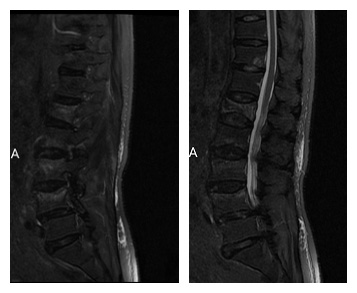

20多天以前,春风送暖,万家团圆,李老爷子一家人沉浸在春节的欢乐中,猝然的不慎摔倒,剧烈的腰痛打破了老人一家的祥和,在经过当地医院初步的检查后,发现老人有四个椎体发生了压缩性骨折,骨折的疼痛以及治疗的需要,老人只能严格的卧床休息,孝顺的家人不得已需要在老人的床前忙前忙后的精心照料。当地医院的医生告诉李老爷子及家人,骨折椎体较多,手术时间长,且患者84岁高龄,手术治疗有困难,如果不手术,就需要至少卧床3个月。老人基础疾病较多,如果卧床3个月,卧床的并发症如骨质疏松、褥疮、肺部感染甚至血栓将会接踵而至,有些并发症会对老人的生命造成严重的挑战。

辗转之下,李老爷子在子女们的积极联系后来到了北京中医药大学第三附属医院,平车推进了病房,找到了脊柱科于栋主任医师。于主任在认真的询问病情、查体、阅片之后,为了让卧床的老人早期站起来,认真评估后决定行微创手术治疗。于主任团队精心做好术前准备和制定手术计划,一个小时完成了四节椎体的微创手术,术后第二天,在于主任的帮助之下,李老爷子戴上腰部支具,下床行走了。